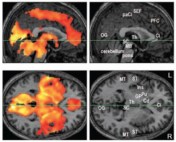

As with most urban legends, origin theories vary, but one of the earliest citations is from the 1936 book, “How to Win Friends and Influence People.”1 The book’s foreword proclaims, “Professor William James of Harvard used to say that the average person develops only 10 percent of his latent mental ability.”2 However, William James, recognized as the “father of American psychology,” never reported such a number.1 Instead, his often referenced line,1,3 “We are making use of only a small part of our possible mental and physical resources,”4 reads more as a philosophical conjecture than a quantifiable biological truth. In fact, the myth can be easily refuted with neuroimaging methods that measure brain activity. For example, even during sleep, fMRI scans demonstrate widespread activation across the brain, including in areas responsible for vision, hearing, touch, and language!5

In Hong et al. (2009), fMRI scans indicate widespread activation in the brain during REM sleep. Left panels indicate areas with statistically significant activity (colored) from sagittal and horizontal sections. Supplementary right panels provide reference for anatomical regions of interest, e.g. OG=occipital gyrus (for vision); ST=superior temporal gyrus (for hearing, language); GP, Pu, Cd= Globus Pallidus, Putamen, Caudate Nucleus (for voluntary motor control).